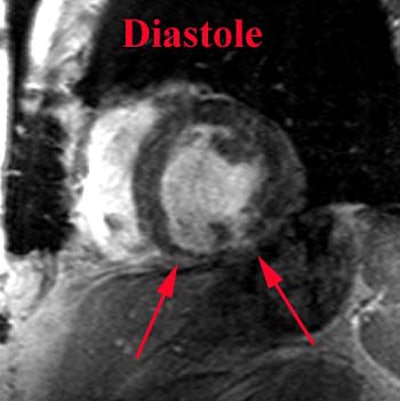

MRI: On MRI, acutely infarcted myocardium demonstrates increased signal intensity on T2 images.

.Prior MI: Below are two short axis views (diastole and systole) from a cine-GRE sequence of a patient with an inferior MI. The examination demonstrates thinning and lack of motion in the inferior wall consistent with an area of infarction. Case from Dr. Scott Flamm. |